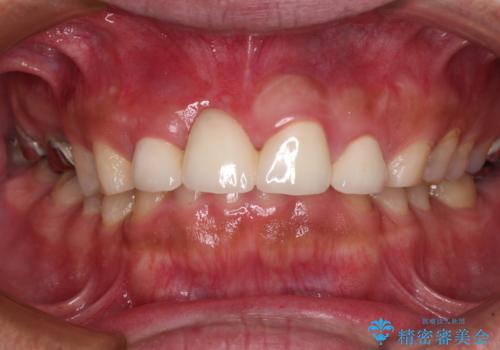

不自然な前歯 歯肉移植を用いた前歯のオールセラミックブリッジ

- 前歯の違和感と不自然な形態のブリッジを気にして来院された患者様です。

歯の幅径のバランスが取れ、自然な口元となりました。